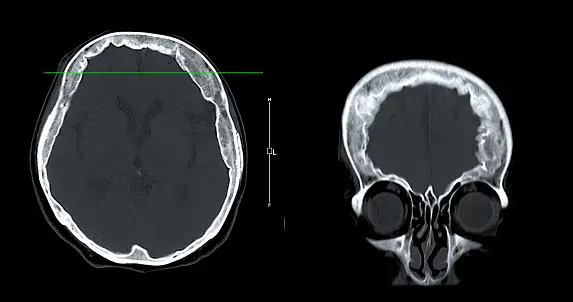

- 컴퓨터 단층촬영(CT): CT는 뇌의 단면 영상을 생성하여 뼈와 같은 뇌 구조의 이상을 확인하는 데 사용됩니다. 종양을 강조하기 위해 대비제를 사용할 수도 있습니다.

최근 뇌종양 진단 분야에서는 혁신적인 기술이 많이 개발되고 있습니다. 이러한 기술은 기존의 진단 방법에 비해 더 정확하고, 비침습적이며, 빠르게 결과를 얻을 수 있습니다. 예를 들어, 자기공명영상(MRI) 검사는 뇌 구조의 상세한 영상을 제공하여 종양의 위치와 크기를 파악하는 데 사용됩니다. 또한, 양전자방출 단층촬영(PET) 검사는 뇌 활동을 영상화하여 종양의 대사적 특성을 평가하는 데 사용됩니다.

## 1. 뇌종양 진단을 위한 혁신적인 기술 혁신적인 영상 기술 자기공명영상(MRI): 뇌종양의 상세한 입체 영상을 제공하여 종양의 크기, 위치, 특성을 정확히 파악할 수 있음. 컴퓨터 단층촬영(CT): 뇌종양의 뼈와 연조직 구조를 시각화하여 종양의 위치와 확산 정도를 평가하는 데 사용됨. 포지트론 방출 단층촬영(PET): 뇌활성을 측정하여 종양 세포의 대사 활동을 검출하고 종양의 악성도를 평가하는 데 사용됨. 분자적 진단 기술 유전자 검사: 뇌종양에서 발견되는 유전자 돌연변이를 식별하여 종양의 유형, 예후, 치료 반응성을 결정하는 데 사용됨. 면역조직화학: 종양 세포의 표면에 있는 특정 단백질을 검출하여 종양의 종류와 특성을 구별하는 데 사용됨. 미세침습적 기술 뇌생검: 종양 조직의 한 부분을 제거하여 종양의 병리학적 진단과 분자적 분석을 위한 검체를 제공함. 액체 생검: 혈액이나 뇌척수액에서 종양 세포나 유전자 물질을 검출하여 비침습적으로 종양 진단과 모니터링을 수행하는 데 사용됨. 기타 혁신적인 기술 인공지능(AI): 의료 영상 데이터를 분석하여 종양을 자동으로 감지하고 특성화하는 데 사용됨. 가상 현실(VR): 외과의사가 수술 중 뇌종양을 시각화하고 제거하는 데 도움이 됨. 3D 프린팅: 환자 맞춤형 수술 가이드 및 임플란트를 제작하여 수술의 정확도와 효과성을 향상시킴.## 1. 최신 뇌종양 진단 기술 최신 영상 진단 기술 자기 공명 영상(MRI): 강력한 자기장과 전파를 사용하여 뇌 내부 구조의 상세한 영상을 생성합니다. 컴퓨터 단층 촬영(CT): X선을 사용하여 뇌의 뼈와 연조직의 단면도를 생성합니다. 양전자 방출 단층촬영(PET): 방사성 동위원소를 주입하여 뇌의 대사 활동을 측정합니다. 분자 영상 기술 MR 분광법(MRS): 뇌의 화학적 프로필을 분석하여 종양과 정상 조직을 구별합니다. 핵의학 영상 기술: 특정 수용체에 결합하는 방사성 표지자를 주입하여 종양의 특성을 파악합니다. 혈액 검사 종양 마커 검사: 뇌종양에서 발견되는 특정 단백질이나 암세포를 탐지합니다. 유전자 검사: 종양의 유전적 특성을 분석하여 맞춤형 치료 계획을 수립합니다. 조직 검사 생검: 종양에서 세포나 조직 샘플을 채취하여 현미경 검사를 통해 종양의 유형과 등급을 확인합니다. 기술적 진보 인공 지능(AI): 영상 분석을 자동화하고 정확성을 향상시킵니다. 가상 현실(VR): 수술 계획과 시뮬레이션을 위한 몰입형 환경을 제공합니다. 3D 프린팅: 환자별 맞춤형 치료 장치 및 모델을 생성합니다. 이러한 기술적 진보는 의료진이 뇌종양을 더 정확하고 신속하게 진단하고 맞춤형 치료 계획을 수립하는 데 도움이 됩니다.